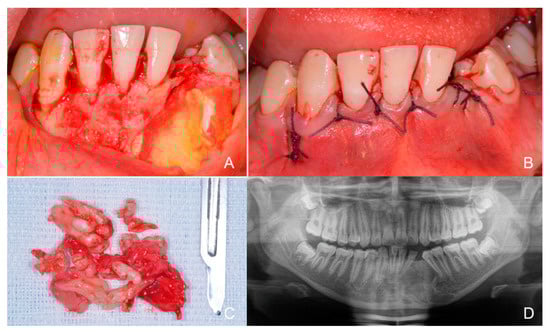

1.2. Case Number 2